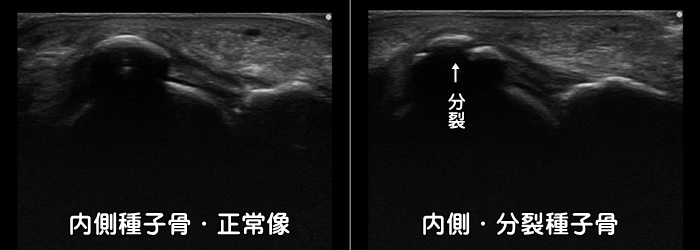

母趾種子骨障害・分裂種子骨

足の母趾の裏側(母趾球部)に痛みがあれば種子骨(しゅしこつ)と呼ばれる小さな骨に炎症が起こっているかもしれません。時に種子骨が割れて分裂しています。分裂していても症状のない方も沢山おられます。